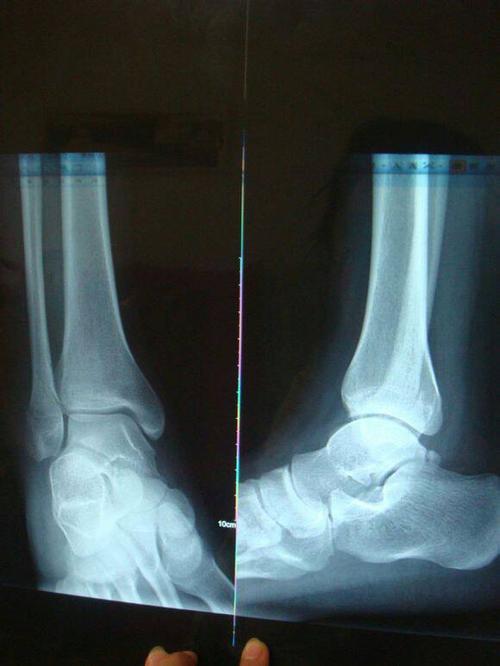

脚踝骨折照片高清图片,脚踝骨折打石膏图片

脚踝骨折及恢复过程记录

3米高处坠落致脚踝粉碎性骨折,仅15天即可下地行走

问:这样的脚踝扭伤严重吗,骨折了吗

网友们大家好,我右外踝腓骨小头游离块,就是外踝撕脱骨折,我今天已经

脚踝骨折打石膏图片

外踝骨折图片

脚踝骨折ct图片清晰